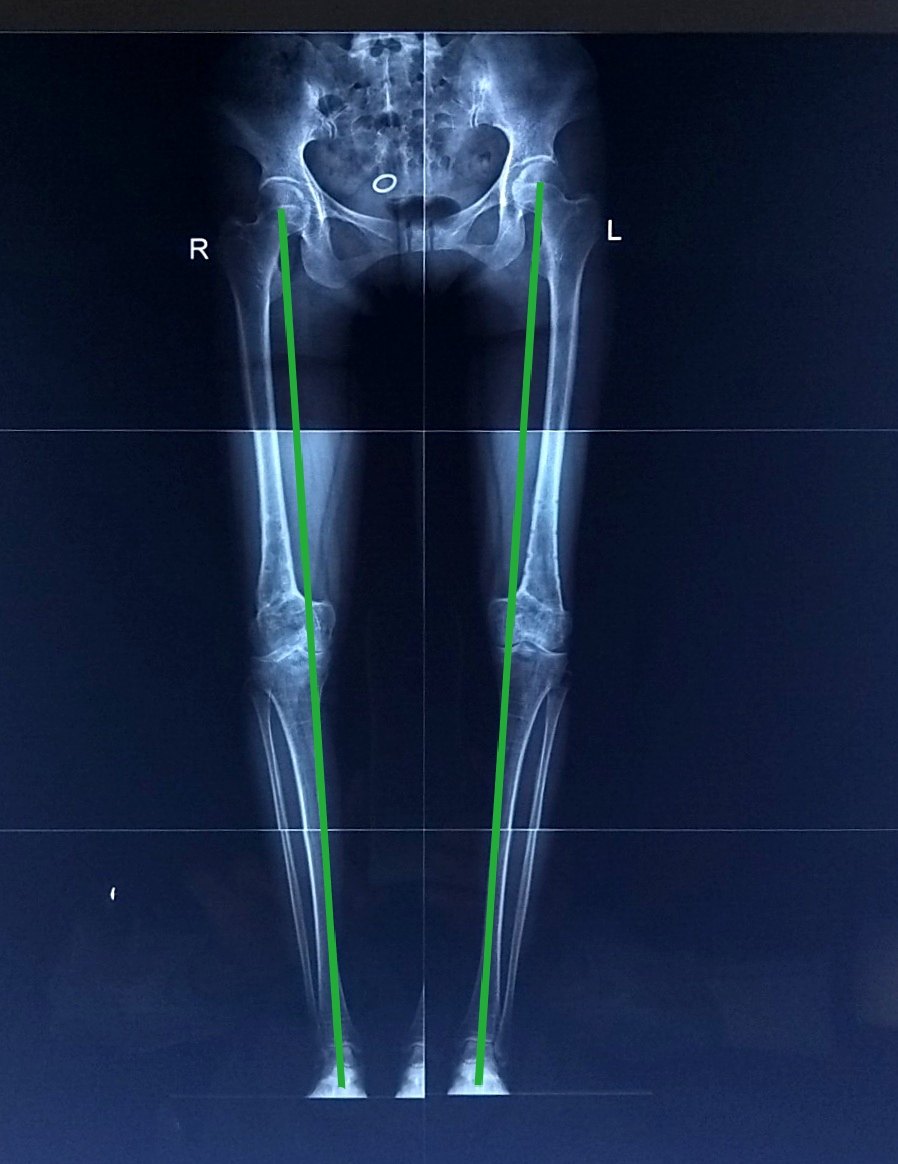

43岁女性,重度外翻膝,疼痛行走困难,双侧截骨矫形术 - 好大夫在线

图片尺寸898x1164